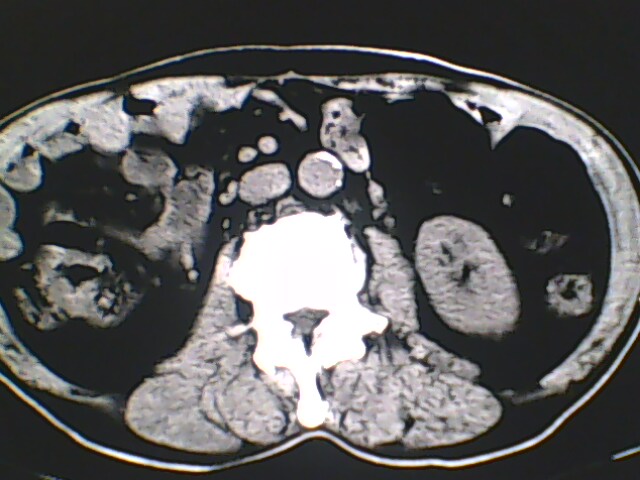

男,56岁,高血压,临床怀疑肾上腺问题,肝脏怎么那么高啊?能描述一下么?

右侧膈膨升,间位结肠,胸腰椎退行性骨关节病,右侧肾上腺可疑增生(图像颗粒太粗,窗太窄,不好看)。

支持 右侧膈膨升,间位结肠;胸腰椎退行性骨关节病;双侧肾上腺可疑增生。

楼主医院的ct机该换了。